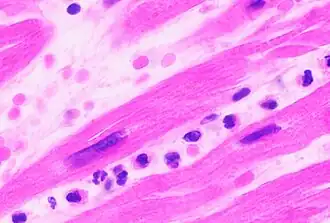

In autopsy, the presence of neutrophils in the heart or brain is one of the first signs of infarction, and is useful in the timing and diagnosis of myocardial infarction and stroke.

-

Neutrophils are seen in a myocardial infarction at approximately 12–24 hours,[67] as seen in this micrograph. -